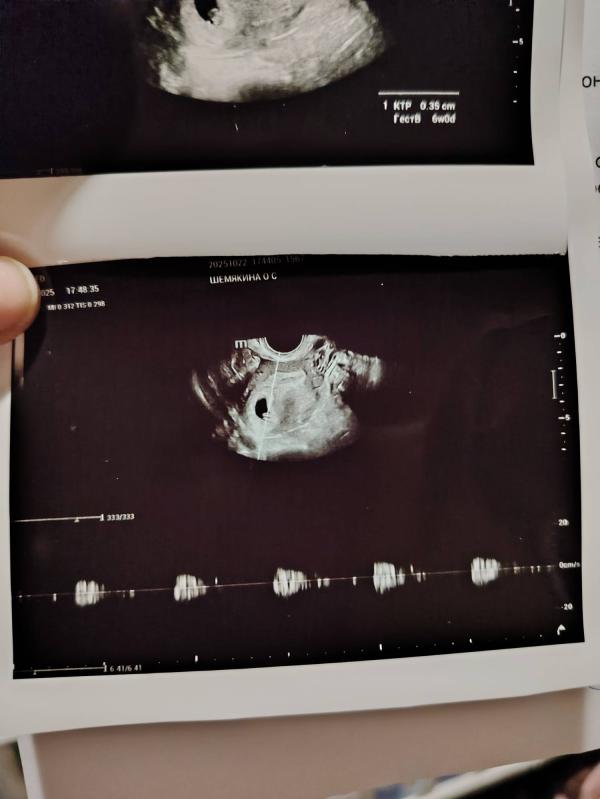

Сходили мы на узи. По узи срок на 4дня отстаёт от срока по месячным. Но думаю это норм. Дочка на 1,5 недели отставала... Человечк пульсирует, даже дали послушать чуток сердечко. Чсс пока не стали записывать. В пн узи в ЖК и плановый приём, наверно и на учёт поставят🙏❤️